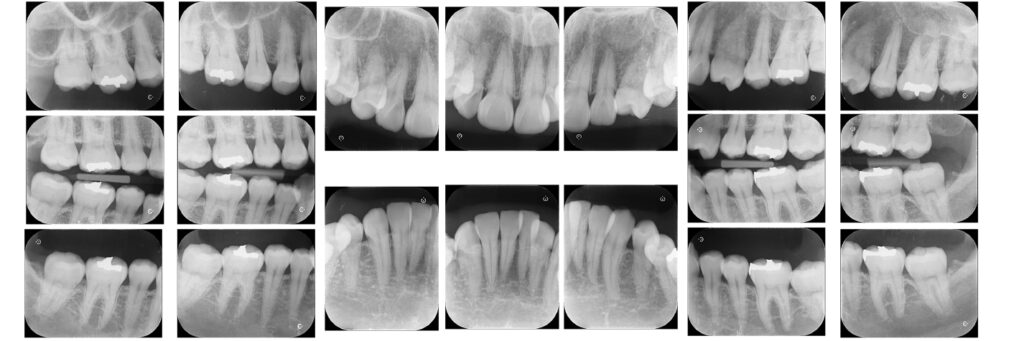

上下の歯列にガタガタ(叢生)が見られます。

上顎左右の3番目の歯が欠損しています。

左上4番が大きく捻転しています。

治療が必要な虫歯はありません。

CTから歯根と骨の状態を確認して歯根の移動の距離を決定します。